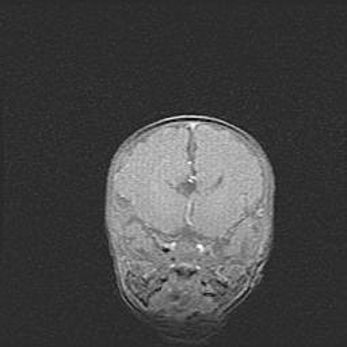

Аномалия Денди-Уокера. Признаки гипоплазии мозолистого тела.

Возраст: 5 месяцев 3 дня

Вес: 5550 г

Пол: мужской

Окружность головы: 39 см

Срок гестации: 40 недель

Аномалия Денди-Уокера – это порок развития головного мозга, для которого характерна триада симптомов: гипотрофия или аплазия червя мозжечка и/или полушарий мозжечка, расширение четвёртого желудочка с формированием ликворной кисты задней черепной ямки, гипертензионная гидроцефалия различной степени.

Гипоплазия мозолистого тела относится к дефектам внутриутробного этапа развития мозговой ткани, возникающим в процессе закладки структур головного мозга, что происходит на начальных этапах развития эмбриона.